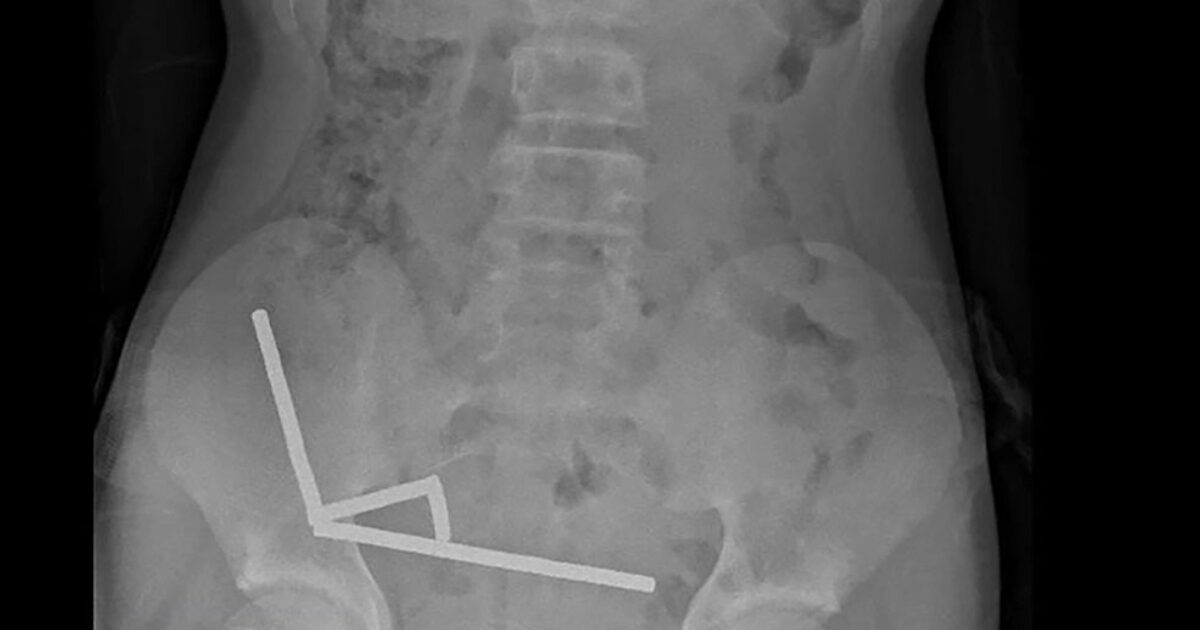

The x-ray showed that the magnets were concentrated in four straight lines inside the child’s intestines, as was also seen on the x-ray.

“They seemed to be in different parts of the gut, which they were get stuck to each other due to magnetic forces,” the report says.